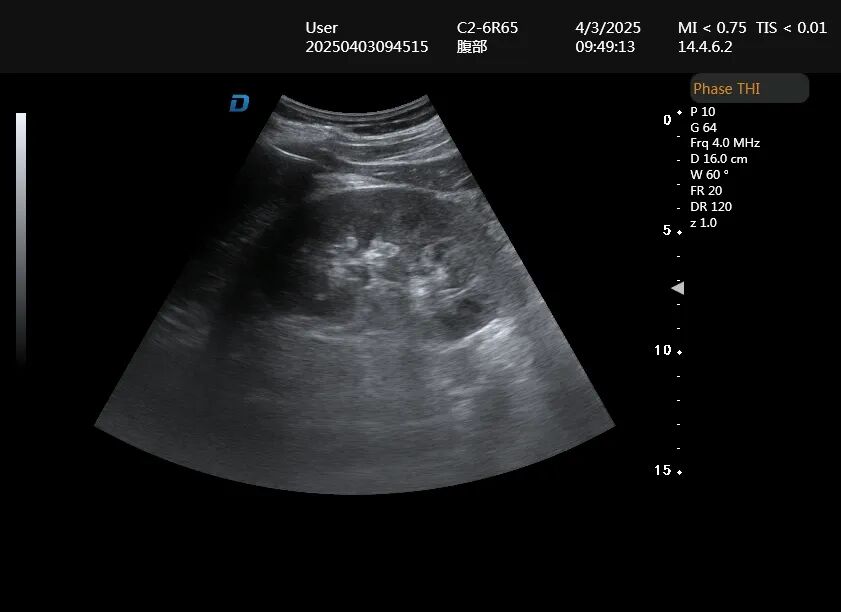

肾脏大小和形态

正常成人肾脏长约10-12厘米,厚约4-5厘米。通过超声测量,医生可以判断肾脏是否萎缩(常见于慢性肾病)或增大(常见于急性炎症、肿瘤等)。肾脏轮廓是否光滑、边界是否清晰,也能反映肾脏健康状况。